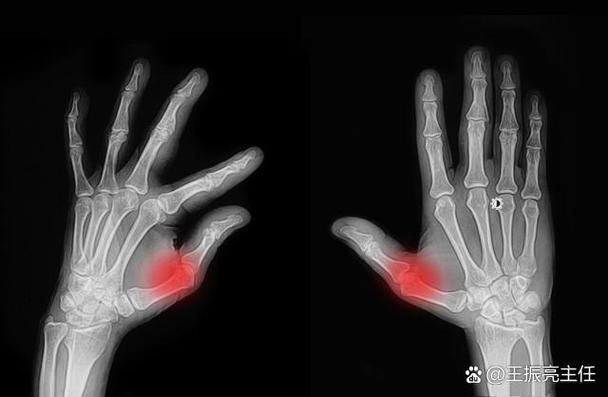

- 它不是“简单的关节病”: RA是一种以侵蚀性、对称性多关节炎为主要临床表现的自身免疫性疾病,是身体的免疫系统“叛变”了,错误地攻击了自己的关节滑膜,导致炎症、疼痛和软骨破坏。

- “早期、达标”是治疗核心: RA治疗的“治疗窗口期”非常宝贵,早期、规范的治疗,可以最大程度地控制炎症,阻止关节结构被破坏,避免残疾,我们的治疗目标不是“不痛就行”,而是达到“临床缓解”或“低疾病活动度”。